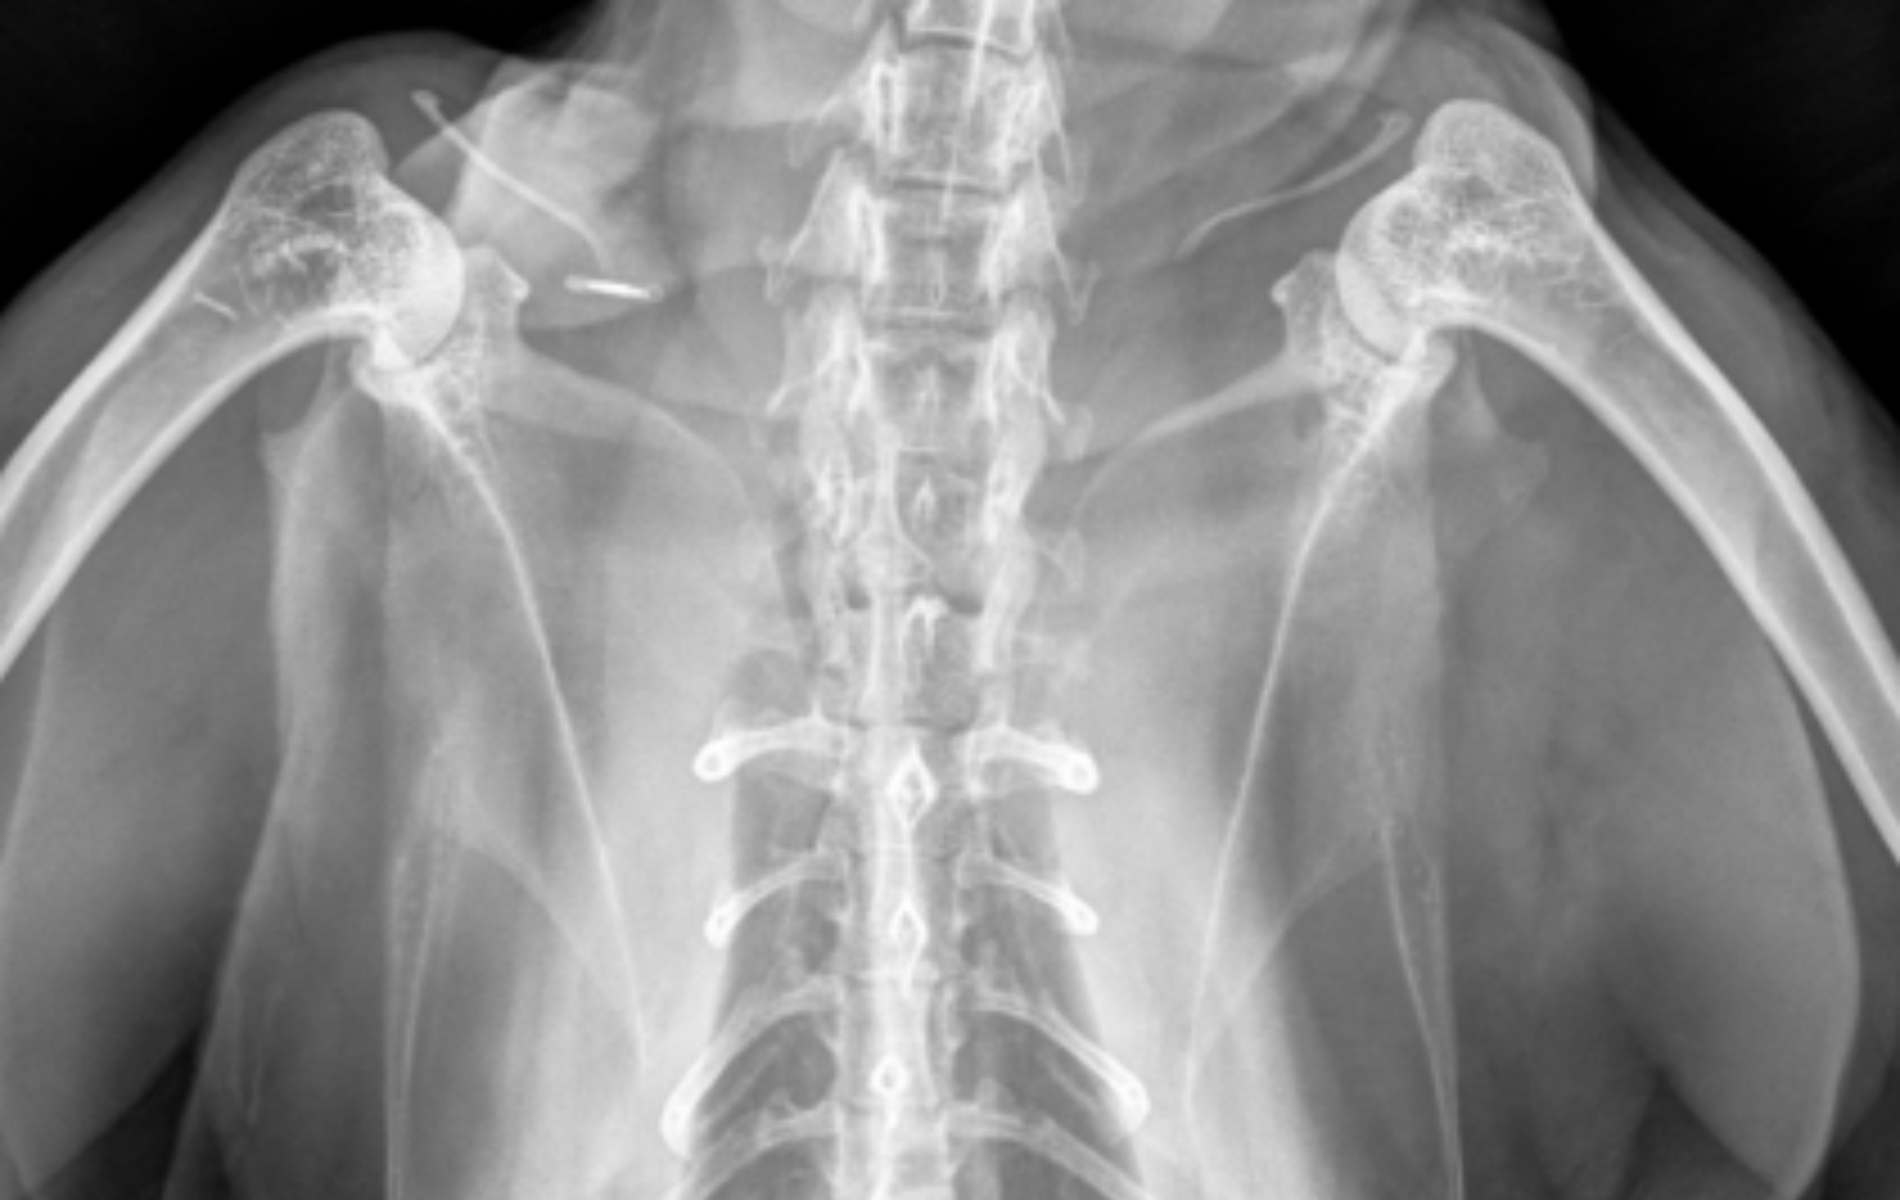

Abdominal

Ultrasound

Echocardiography

Radiography (COMING SOON)